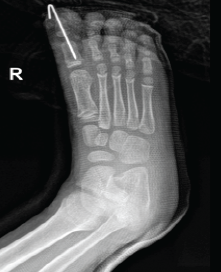

Open Dislocation of Hallux Interphalangeal Joint in a Child: A Rare Case Report

Demah M Benfaris , Aref A Altawair , Abdulnasser Alwabel , Fahad S Alhuzaimi

………………………………p.174-177